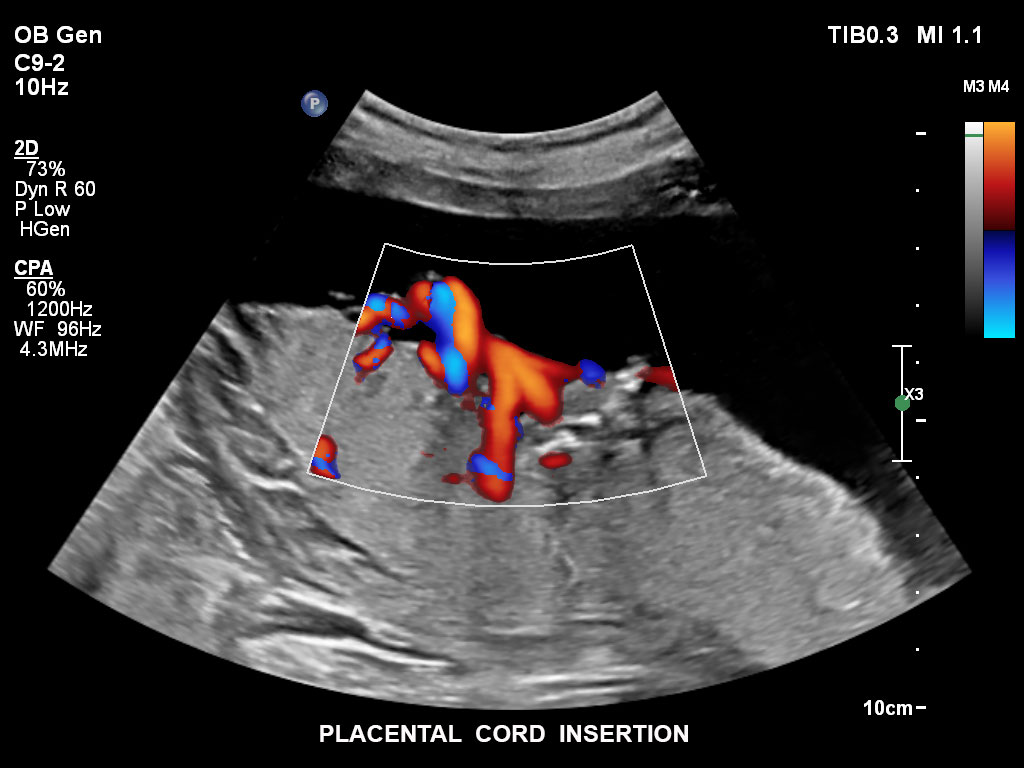

• C9-2 PureWave-Breitband-Convex-Schallkopf für Hochfrequenz-Bildgebung in der Gynäkologie und der Geburtshilfe, insbesondere für die Untersuchung im Hinblick auf mögliche Anomalien im ersten Schwangerschaftstrimester